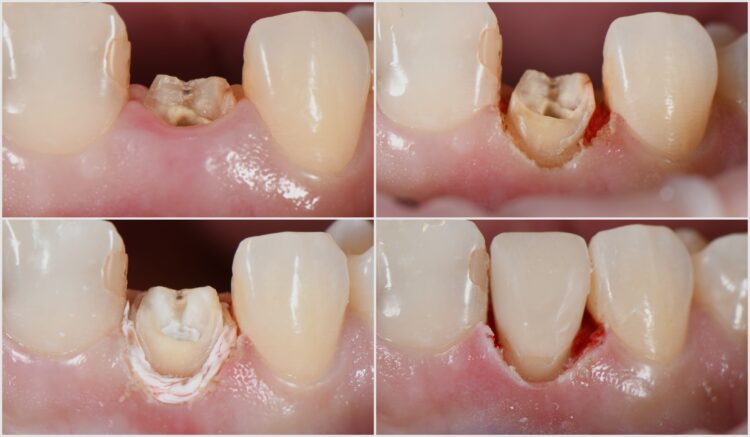

Mikroskopická endodoncie / reendodoncie

Primární nebo sekundární ošetření kořenových kanálků za pomoci operačního mikroskopu.